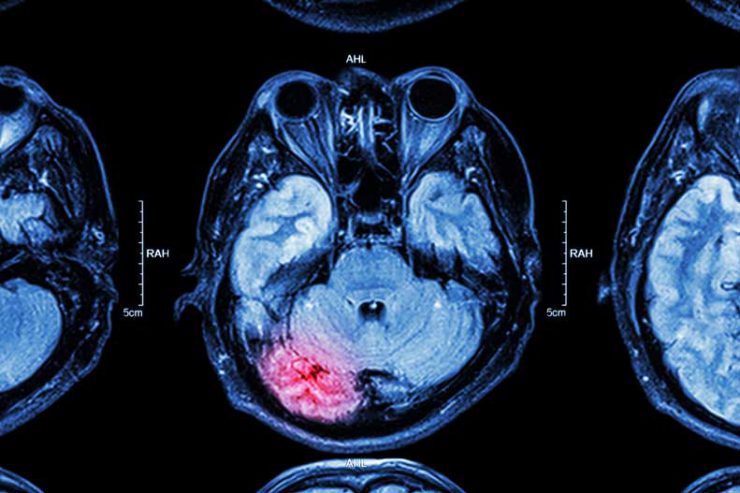

Ekzaminimet mund të fillojnë kur jeni ende në ambulancë. Sapo të arrini në repartin e urgjencës, do t’ju kryhen teste imazherike të tilla si Skaner CT, Rezonanca Magnetike -MRI ose ECHO. Mund t’ju kryhen edhe lloje të tjera ekzaminimesh, të tilla si një EKG (kontrollon aktivitetin elektrik të zemrës suaj) apo një EEG (kontrollon aktivitetin elektrik të trurit tuaj).

Strok-u hemorragjik

Goditjet hemorragjike ndodhin kur një enë e dobësuar e gjakut në tru shpërthen. Rezultati i kësaj është gjakderdhja brenda trurit që mund të jetë e vështirë të ndalet. Shkaku më i zakonshëm është presioni i lartë i gjakut. Shkaqe të tjera përfshijnë aneurizmat dhe AVM-të (keqformime arterio-venoze), të cilat dobësojnë enët e gjakut në tru.